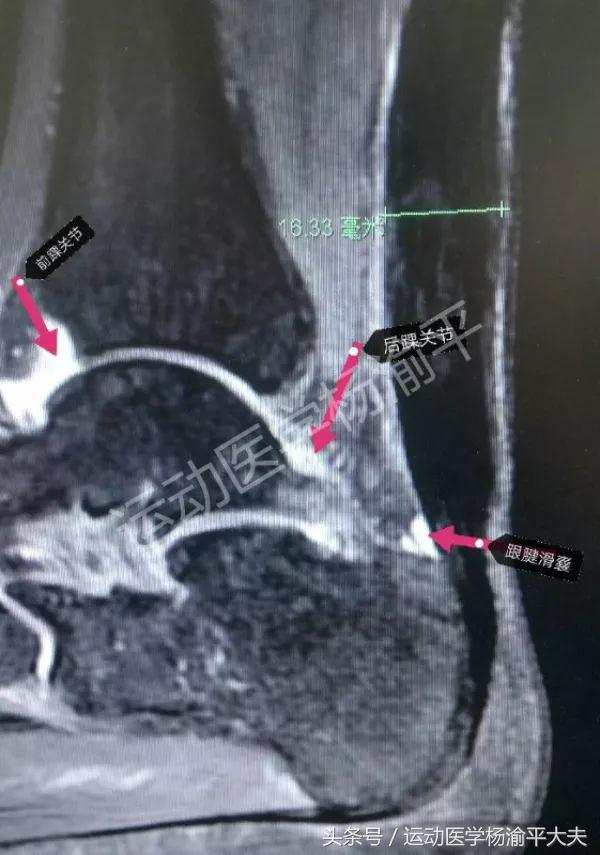

(图二)

为了证实这一点大家图二这张核磁图的例子,这是一个跟腱陈旧断裂的病人的核磁,按理说应该只有跟腱显示有一定的问题,但是他的踝关节里面同样有关节积液。事实上,这个病人的踝关节根本就没有受过伤,也没有任何其他不适的症状,这个跟腱也早就断了半年了,理论上来说,也不应该对踝关节产生什么特别严重的影响。包括还有我们人体的正常有一些滑囊,有一些有炎症的;或者甚至没有炎症的,那里头也可以有少量的积液,这些少量的积液就是为了起到非常重要的营养和润滑的作用。